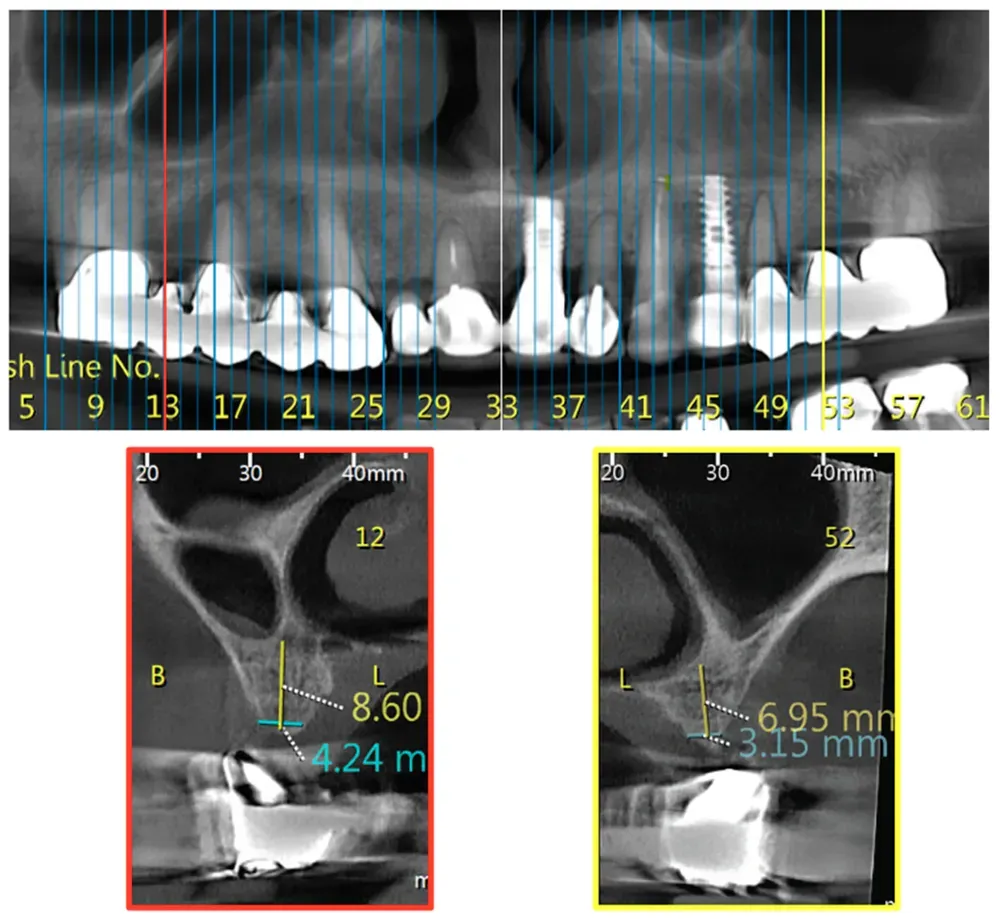

Queste caratteristiche anatomiche possono essere diverse tra un lato e l’altro. È possibile riscontrare una classe su un lato e una morfologia diversa sull’altro. Vedi le immagini che seguono.

La distribuzione verticale rivela pattern ancora più interessanti, classificati dagli autori in divisioni. Vedi figura sotto.

Da sinistra a destra—Sezioni trasversali CBCT: Divisione A (Div. A): Cavità nasale da sola; Divisione B (Div. B): Cavità nasale adiacente alla cavità sinusale; Divisione C (Div. C): Cavità sinusale da sola sopra la cresta alveolare; Divisione D (Div. D): La cavità nasale è posizionata in posizione superiore rispetto alla cavità sinusale. Da Yahya et al. (2021). Licenza CC4.0.